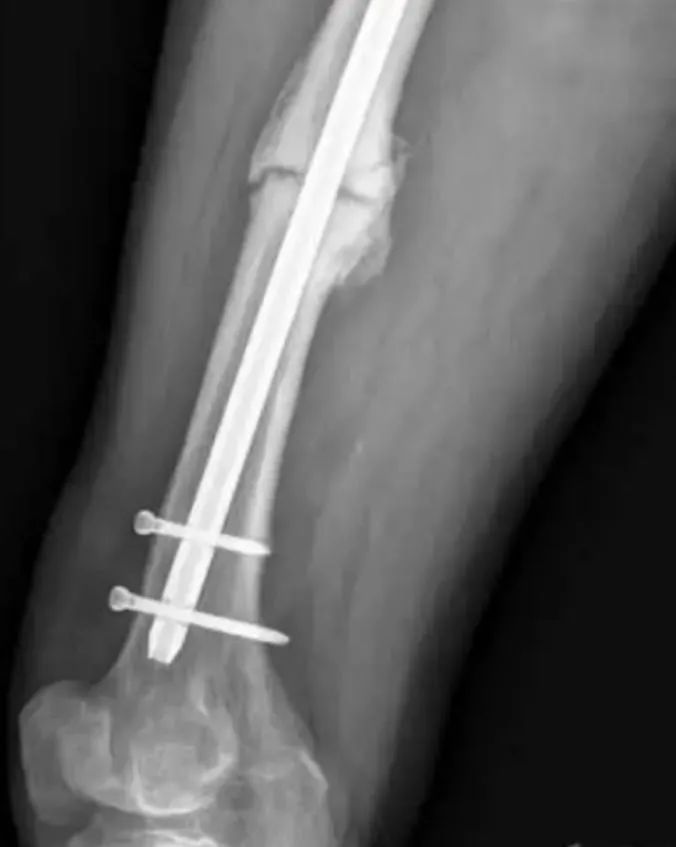

Удаление сломанного интрамедуллярного гвоздя является сложной задачей.Неудачи внутренней фиксации обычно связаны с усталостными отказами из-за повторяющихся подпороговых нагрузок.Во время вторичного процесса заживления костной мозоли интрамедуллярный ноготь стимулируется повторяющимися деформационными силами.По сравнению с более ранними интрамедуллярными стержнями с прорезями, новые закрытые интрамедуллярные стержни с поперечным сечением более устойчивы к таким силам деформации.Точно так же увеличение диаметра может улучшить антиусталостные свойства интрамедуллярного стержня.Когда интрамедуллярный стержень сломан, это указывает на то, что в конце перелома все еще есть движение, поэтому перелом интрамедуллярного стержня можно рассматривать как один из признаков несращения;в этом случае необходимо удалить интрамедуллярный стержень для дальнейшего лечения.

После установления диагноза несращения следует рассмотреть вопрос об удалении интрамедуллярного стержня до его разрыва.Часто трудно определить момент разрыва интрамедуллярного стержня, поэтому вопрос о том, когда следует удалять интрамедуллярный стержень, является спорным.Однако удаление интактного интрамедуллярного стержня намного проще, чем удаление сломанного интрамедуллярного стержня, поэтому хирург должен учитывать этот фактор при последующем лечении.